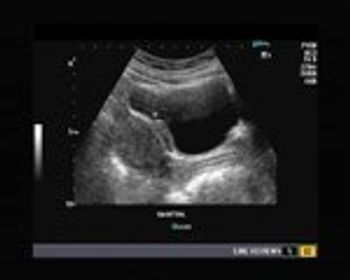

Our patient is a 30 year old female with a history of mild pain during micturition.

This is an ultrasound scan of the pelvis in 35 year old female patient.

Using only this image, describe what phase of the menstrual cycle this patient is in.